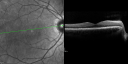

OD: Vertical C/D ratio is 0.2. There is no posterior vitreous separation and 2+ multiple macular drusen. There is no bull’s-eye maculopathy.

OS: Vertical C/D ratio is 0.2. There is no posterior vitreous separation, again there are 2+ multifocal small cuticular macular drusen.

OCT SCAN: The OCT scans were normal. Photos confirm clinical findings.

FLUORESCEIN ANGIOGRAPHY: Fluorescein angiography shows early hyperfluorescence of tiny macular drusen scattered throughout the macula in both eyes.